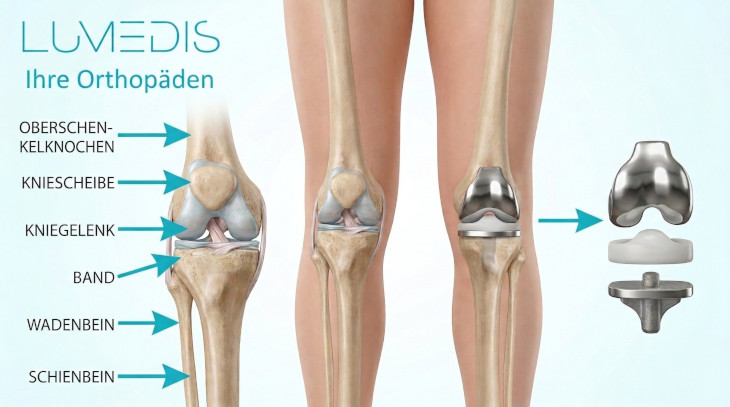

Unter einer Knieprothese versteht man einen künstlichen Ersatz des Kniegelenks.

Welche Arten von Knieprothesen gibt es?

Die Knieprothesen können nach verschiedenen Gesichtspunkten eingeteilt werden.

Allgemein wird unterschieden zwischen dem Ersatz des gesamten Kniegelenks und einem Teilersatz:

- Die Knie-Totalendoprothese (KTEP) umfasst dabei den künstlichen Ersatz aller Gelenkanteile, also dem Oberschenkel- und Schienbeinknochen, sowie in einigen Fällen auch der Kniescheibenrückseite.

- Eine Teilendoprothese ist im Gegensatz zur TEP unikondylär, was bedeutet, dass hier nur die innere oder äußere Knochenrolle des Oberschenkels mit dem entsprechend gegenüberliegenden Schienbeinplateau ersetzt wird.